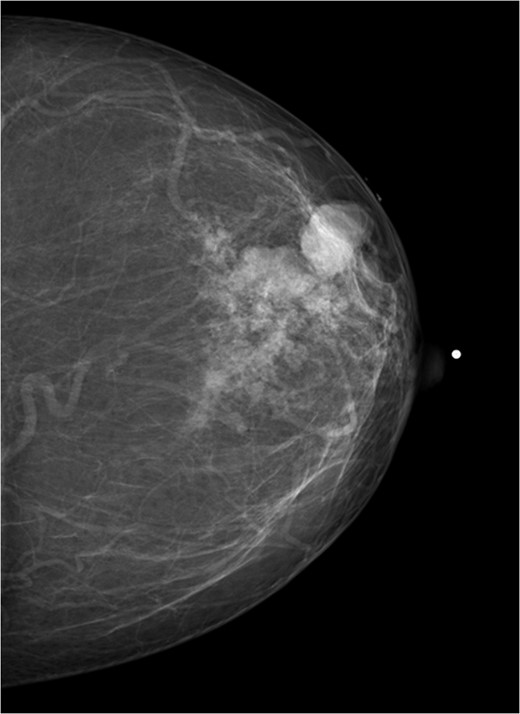

A 56-year-old black female presented to the surgical clinic with a palpable left breast mass that had grown over several months. She denied nipple discharge, breast retraction or family history of malignancy. Physical exam revealed a palpable, subareolar mass without skin changes or asymmetry, and no lymphadenopathy. Her mammogram revealed a 5.4 × 3 cm lesion behind the nipple with Breast Imaging-Reporting and Data System (BI-RADS) 5 classification. An ultrasound indicated a 2.2 × 2 cm lobulated hypoechoic mass with BI-RADS 4 classification (Figs 1–3).

Mammogram mediolateral view of left breast showing lesion posterior to nipple BI-RADS 5.